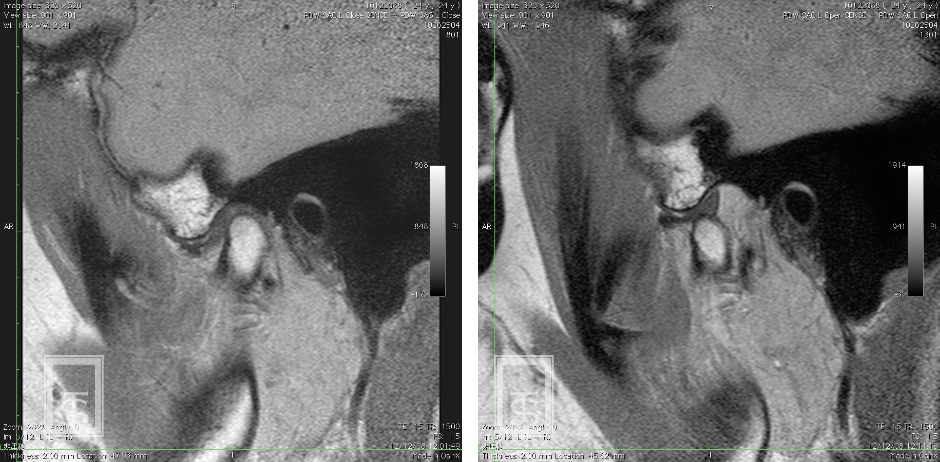

顎関節内障とは?

顎関節内障とは顎関節に器質的変化のある状態(関節円板の転位および下顎頭骨変化)をさします。

一般的に復位性円板転位では、開口時の関節雑音を伴い、非復位性円板転位では、開口障害を生じます。

慢性化すると症状は様々です。

- 顔貌、口腔内、模型、機能、レントゲンなどの診査を行います。

必要に応じてCT、MRIの撮影も行います。